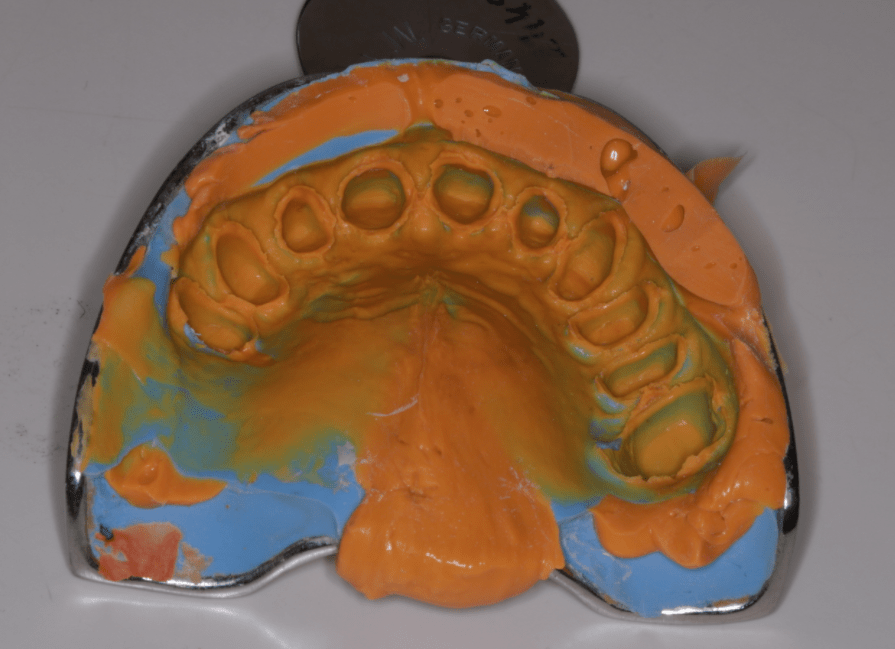

Első lépésként előkészítettem a fogakat a pótláshoz (szuvas léziók eltávolítása, csonkkiegészítések kompozit tömőanyaggal, csonkpreparálás), és levettem a szükséges lenyomatokat.

Majd ezt követően arcívvel meghatároztam a felső állcsont koponyához való elhelyezkedését, intraorális rajzolóeszközzel a felső és az alsó állcsont egymáshoz való viszonyát, majd az Arcus Digma készülékkel az individuális mozgáspályákat. Ez mind szükséges ahhoz, hogy egyedi, az egyén számára legkényelmesebb fogpótlás elkészülhessen, melytől jelen esetben páciensünk panaszainak rendeződését vártam.